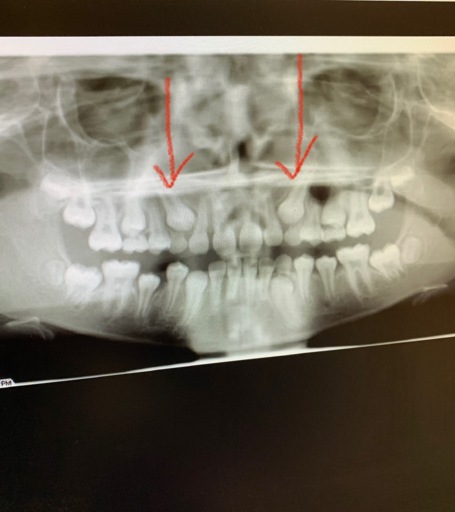

I had upper jaw surgery 18 years ago. Over the last few weeks I have been having pain in my upper jaw on the right side near my ear. It's getting worse, stabbing and shooting pain. It gets worse when I chew. Should I be concerned or can I do anything for it?.... I also had surgery on my tongue and chin the same summer as my upper jaw surgery and also had all 4 of my wisdom removed

Having pain in your jaw or near you ear is not normal and you should have it checked out.  It could be an issue with your temporomandibular joint, or a side effect from your previous surgeries.  An oral surgeon can take a panoramic x-ray or a CT scan in order to see the joint, condyles and surround bone to be sure there are no abnormalities.  Preventative measure can be taken in order to reduce inflammation in the area if necessary and restore you to normal function without pain.